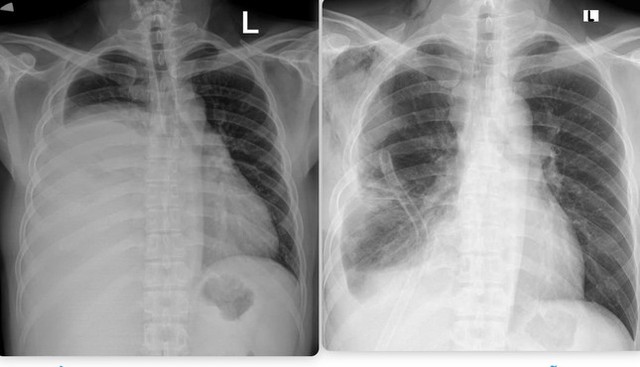

Hình ảnh phim chụp X.quang trước và sau khi phẫu thuật. Hình trước phẫu thuật (bên trái).

Kết quả chụp cắt lớp vi tính cho thấy một khối u khổng lồ nằm lệch trong khoang màng phổi phải, gây xẹp gần như hoàn toàn phổi bên phải và đẩy lệch cơ hoành. Các bác sĩ xác định đây là u bao sợi thần kinh Schwannoma – một dạng u lành tính nhưng rất hiếm gặp và có kích thước "ngoại cỡ".

Sau khoảng 2 giờ căng thẳng, khối u nặng 3,6kg đã được lấy ra trọn vẹn, phổi phải của bệnh nhân giãn nở trở lại, phục hồi hình thái và chức năng hô hấp.